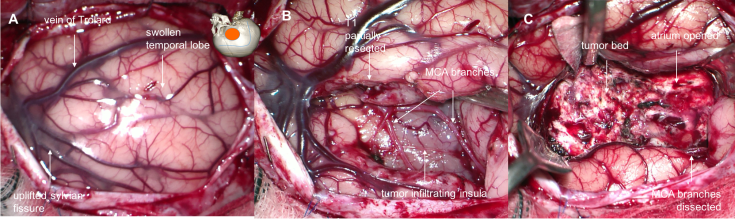

les tumeurs insulaires

elles peuvent être localisées à l’insula, ou l’envahir à partir de la région temporale ou frontale. en profondeur, elles sont en contact avec les noyaux gris centraux et la capsule interne.

- on les aborde en ouvrant la vallée sylvienne, en restant sur le versant temporal pour éviter de léser la région frontale postérieure

- les branches de la sylvienne sont séparées du cortex insulaire tumoral

- la dissection vasculaire peut entraîner un vasospasme, elle devra donc être particulièrement douce.

- il est préférable chaque fois que possible de réaliser une dissection sous-piale pour limiter la contamination de la vallée sylvienne, puis de suivre les limites tumorales.

- la partie postérieure du pédicule temporal contient les radiations optiques, et doit être respectée.

- la résection tumorale se fait par aspiration pour limiter le plus possible la dissection profonde d’avec la capsule interne et les noyaux gris.